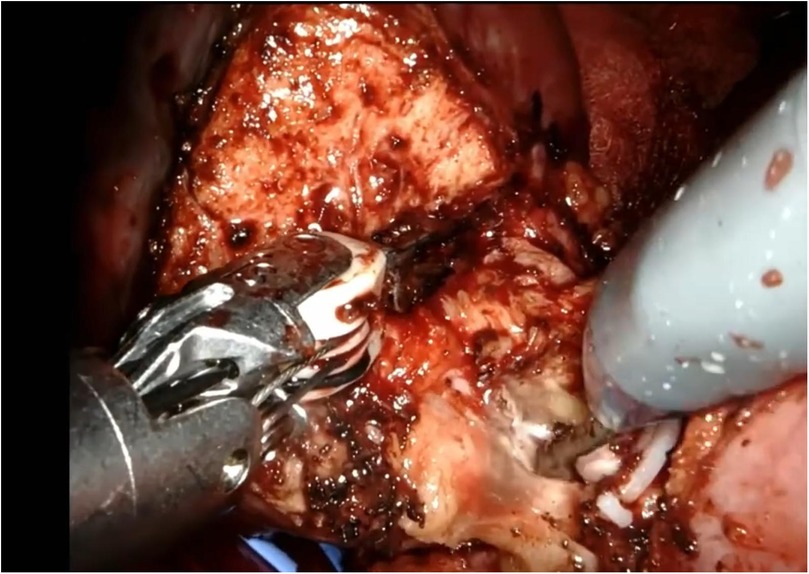

Figure 7

Surgical view showing medical instruments working on a tissue area. The scene is detailed, with visible textures of the tissue and surrounding structures. The instruments are metallic and held at an angle, indicating precision work in a clinical setting.

Figure 7. Enucleation phase.